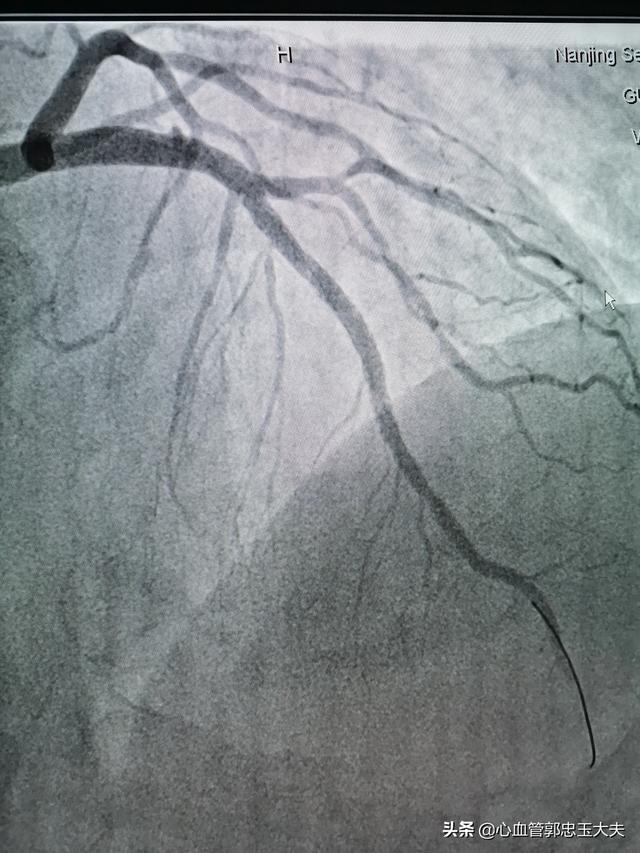

4. la coronarographie. La coronarographie reste l'examen de référence pour le diagnostic des maladies coronariennes, mais elle est invasive et nécessite une hospitalisation.

2. angiographie coronaire

Il s'agit actuellement de l'étalon-or du dépistage cardiovasculaire, qui est intuitif et permet de connaître à temps les interventions, mais il est coûteux et peut être dangereux.

Deuxièmement, pour les personnes qui ressentent souvent une oppression, une distension, une douleur et une gêne dans la région précordiale, voire une douleur irradiant vers le dos, les dents et sous la poitrine, il est préférable de vérifier les enzymes cardiaques et les marqueurs de lésions myocardiques, car les personnes qui présentent ces symptômes peuvent souffrir d'un infarctus du myocarde, et il est préférable de vérifier les profils des enzymes cardiaques ainsi que les marqueurs de lésions myocardiques afin de valider et d'évaluer la gravité de l'infarctus du myocarde dans l'état de santé du patient. Enfin, pour certaines personnes âgées qui ressentent une panique, une oppression thoracique et un essoufflement lorsqu'elles marchent, qui peuvent ou non être soulagés par le repos, et qui présentent souvent un œdème généralisé, il est préférable de vérifier les marqueurs de l'insuffisance cardiaque, c'est-à-dire le BNP, afin de confirmer et d'évaluer la sévérité de l'insuffisance cardiaque du patient. Pour les personnes qui présentent des symptômes de maladie coronarienne mais dont les résultats des tests sont tous négatifs, il est possible de procéder à une angiographie coronarienne du cœur pour confirmer la présence ou non d'une maladie coronarienne, car l'angiographie coronarienne est l'étalon-or de la maladie coronarienne !

L'angiographie coronarienne est principalement utilisée pour diagnostiquer les maladies coronariennes et pour déterminer s'il y a un rétrécissement ou une occlusion des vaisseaux sanguins du cœur ! L'angiographie coronaire est simple et peut être réalisée en ambulatoire, alors que l'imagerie nécessite généralement une hospitalisation !

En outre, si vous souhaitez observer l'état des vaisseaux sanguins du cœur, vous pouvez d'abord procéder à une angiographie coronarienne afin de déterminer si les vaisseaux sanguins sont calcifiés ou rétrécis, ainsi que le degré et l'emplacement du rétrécissement. Toutefois, il ne s'agit là que d'un examen préliminaire. Pour refléter avec précision l'état des vaisseaux sanguins, une coronarographie est également nécessaire ; une fois les problèmes détectés par cet examen, la pose d'une endoprothèse et d'autres traitements peuvent être effectués en temps utile.

Chez un patient atteint d'une maladie coronarienne, un électrocardiogramme bien établi, un électrocardiogramme ambulatoire et une épreuve d'effort sont nécessaires pour déterminer indirectement l'ischémie myocardique. L'échographie cardiaque 2D permet de déterminer s'il existe une ischémie myocardique en fonction du mouvement de la paroi ventriculaire. La scintigraphie nucléaire du myocarde peut déterminer s'il y a une ischémie myocardique par la présence de défauts de remplissage et peut également déterminer la fonction cardiaque. L'angio-tomodensitométrie coronaire (CT angiography) et la coronarographie permettent de déterminer l'emplacement et l'étendue des sténoses et des calcifications. L'infarctus aigu du myocarde est également pris en compte pour améliorer les marqueurs de lésions myocardiques.

Deuxièmement, l'imagerie. L'angiographie est principalement une coronarographie, qui est une technique d'examen relativement avancée permettant de détecter la portée et l'étendue des lésions des artères coronaires.

IV. angiographie coronaire

La coronarographie est la technique de référence pour le diagnostic de la maladie coronarienne. Elle permet d'observer et d'évaluer visuellement le trajet et la perméabilité des vaisseaux des artères coronaires, d'évaluer la présence ou l'absence de lésions des artères coronaires et l'étendue des lésions, et d'évaluer la fonction du cœur gauche, ce qui permet d'effectuer une thérapie interventionnelle en fonction de l'étendue des lésions des artères coronaires et d'évaluer l'effet du pontage coronarien et de la thérapie post-interventionnelle. En tant que technique diagnostique invasive, la coronarographie présente certaines contre-indications, telles que l'allergie à l'iode et au produit de contraste, l'insuffisance cardio-pulmonaire sévère, l'insuffisance hépatique et rénale, l'arythmie cardiaque et les troubles électrolytiques, qui ne peuvent pas être effectuées afin d'éviter les accidents.